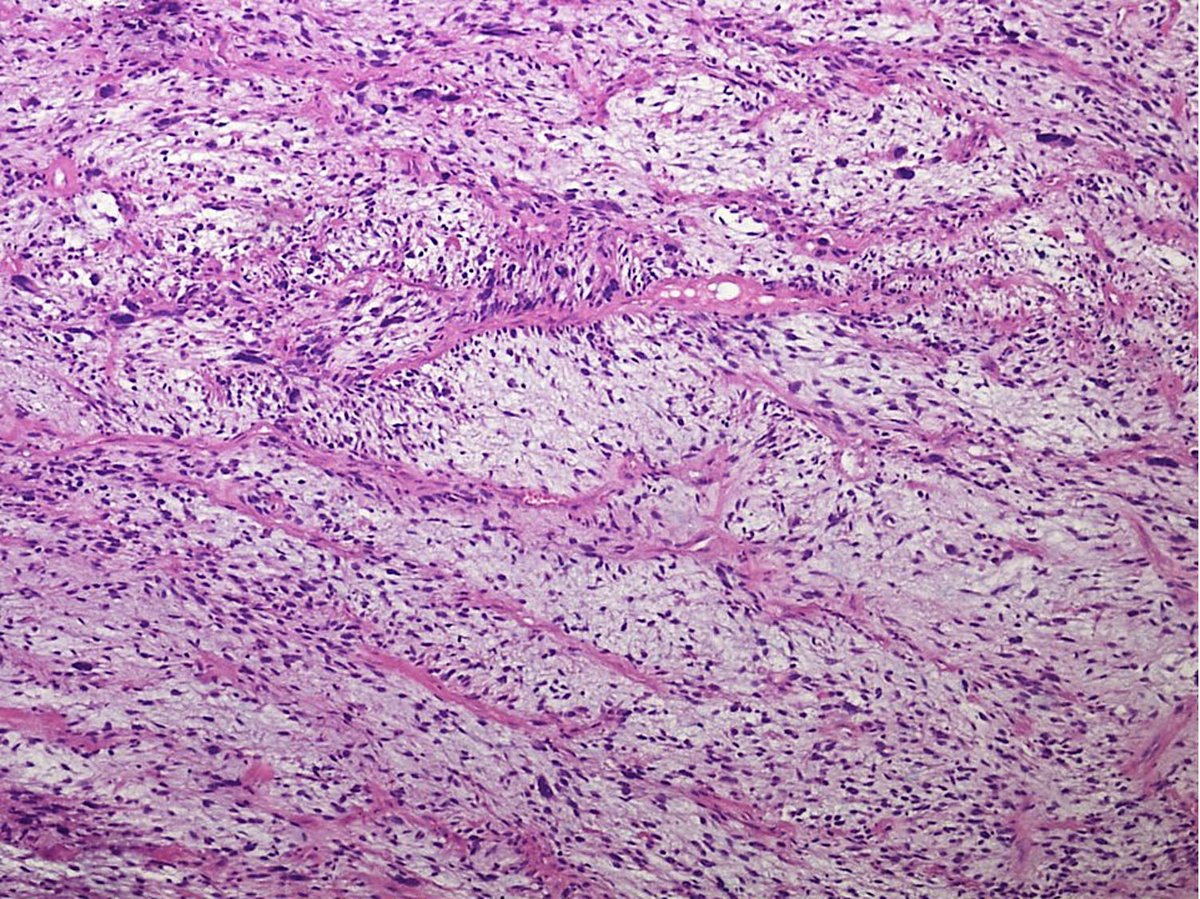

@Pathology_mcqs

Pathology mcqs

3 years

A 48 year old male presented with submandibular swelling for 3 weeks.On examination the swelling was painless, solid, firm and immobile. Excision was performed. Hand E stained section of the tumour is shown below. What is your diagnosis? #pathtweetorial #pathboards #pathresidents